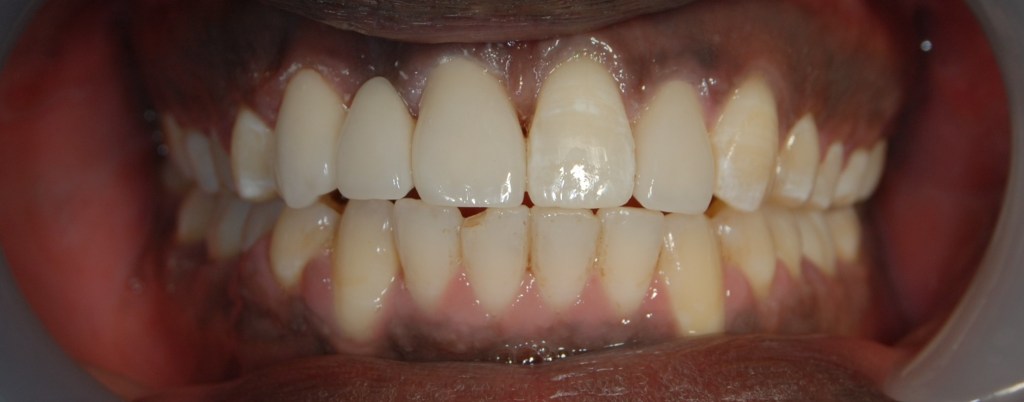

Kozmetikai és funkcionális kezelés: felső torlódott fogak kiegyenesítése, koronák enyhe kifele döntése, mélyharapás korrigálása.

A választott korona típusa: CAD/CAM (komputer vezérelt tervezés/megmunkálás) technológiával készült cirkónium (fémmentes) szóló koronák.

A választott fogszín: A2

A protetikai munka elkészülésének ideje: 5 munkanap.